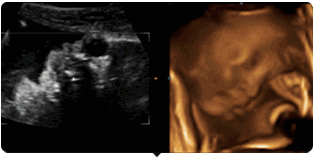

你可以通过美国GE-730高清四维彩超

看到胎宝宝最可爱撩人的画面——

好困,打哈欠